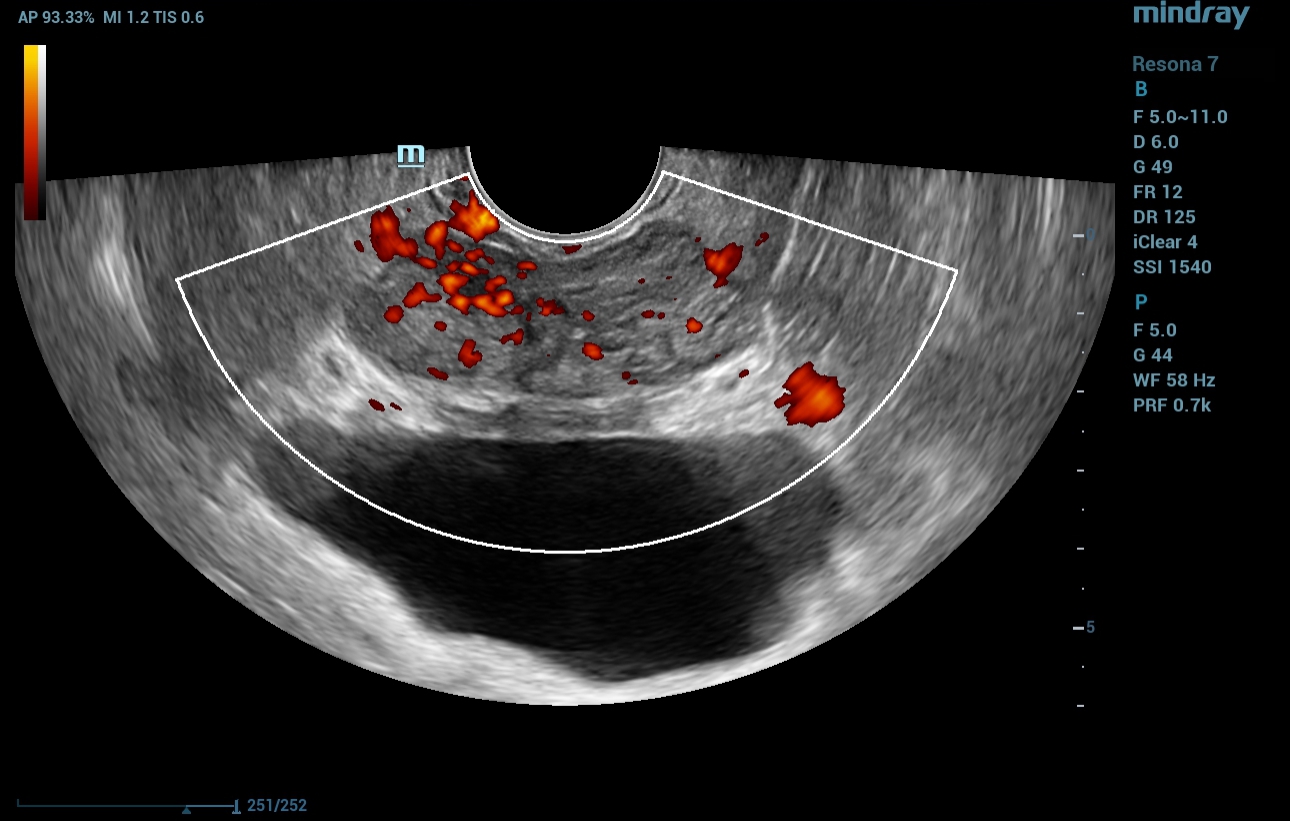

In power Doppler mode, an asymmetric increase in vascularity was seen within the hypoechoic lesion noted on B-mode TRUS imaging (Fig. 2).